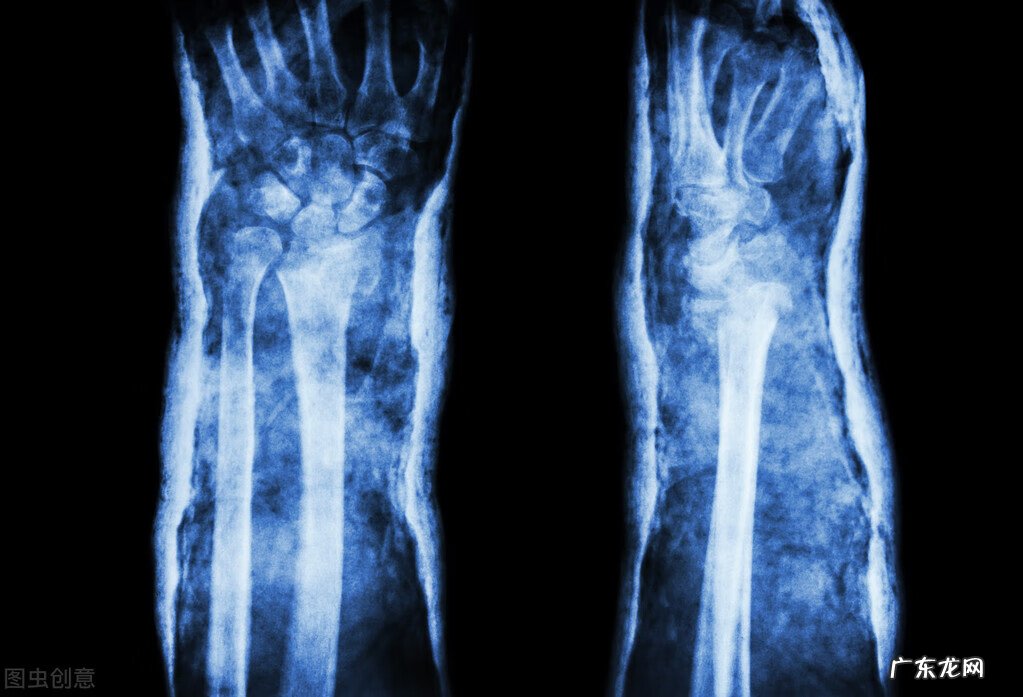

骨折作为一种常见的外科疾病,经常在我们身边发生,尤其是小孩子和老人,由于骨骼的发育或是骨质的影响,导致这些人群,成为骨折的高发人群,尤其是年纪较大的人群,对于年轻人来说一个很小很轻微的摔倒对他们来说都是非常致命的,老年人出现骨折后不易恢复,并且常会累及身体的其他部分,严重者甚至危害生命 。

骨折的发生多由于外部的撞击所致,当冲击力过大高于骨折自身所能承受的力量时,骨折就会发生,当骨折发生时,常有以下的表现,我们也可以通过以下的几方面的表现来判定对象是否出现了骨折,出现各种程度的骨折: